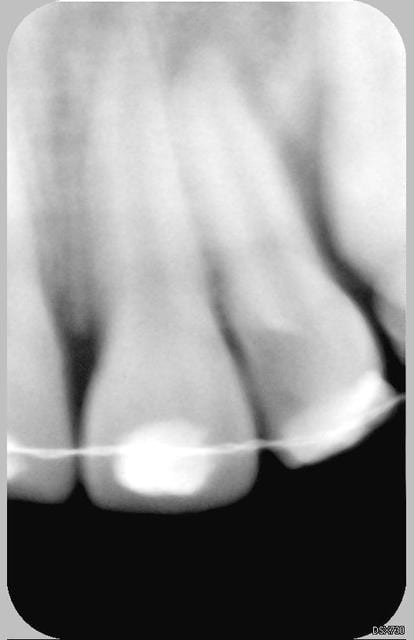

Patiente de 11 ans ayant la 21 expulsée début avril 2006. La dent a été repositionnée en centre de soins. Dans un premier temps, pas de perte de sensibilité. Puis dans un deuxième temps, comme un goût de ça tourne mal avec certainement rhyzalyse interne de la 22 (traitement thermafil pas d'école).

la on est dans un tres beau cas de resorption inflammatoire des 21 et 22

Ci joint la première radio de ces dents avec attelles centre de soins universitaire